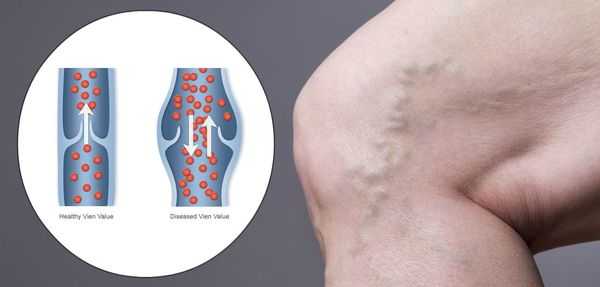

Синдром венозной гипотонии

Синдром венозной гипотонии еще мало изучен и практически не диагностируется в практической медицине. Необходимость изучения этого вопроса состоит в том, что, наблюдая больных с признаками резчайшей слабости при нормальном артериальном давлении, мы вынуждены были искать пути понимания этого состояния.

Основные проявления венозной гипотонии связаны со снижением периферического давления в венозной системе с частичным снижением внутритканевого давления, которое играет (может быть, весьма существенную) роль в гемодинамике. Причины снижения венозного давления скорее связаны со снижением тонуса симпатической нервной системы, которая регулирует венозный тонус. Последствия этого явления имеют существенное значение для состояния гемодинамики.

Наибольшее значение для клиники имеет состояние секвестрации крови в результате гравитационных процессов. Второе клинико-гемодинамическое значение — снижение притока крови к сердцу, что влечет временное снижение УО. Последнее обстоятельство отражается на состоянии ЦНС и коронарном кровотоке. Отсюда состояние дурноты, обморока, появление болей в области сердца в результате снижения кровотока в этом регионе.

Основные показатели венозной гипотонии, особенно в ее критическом состоянии, это прежде всего снижение ВД ниже 100—90 мм рт. ст. Цифры от 60 до 40 мм рт. ст., как правило, сочетаются с состоянием дурноты, головокружением и обмороком («венозный коллапс»). Снижение венозного давления не может не отразиться на состоянии сердца. По нашим данным, снижение притока к сердцу влечет за собой снижение ударного выброса, и только за счет учащения ЧСС сохраняется гемодинамика.

Снижение ударного выброса отражается на мозговом кровотоке. Отсюда характерное для коллапса состояние.